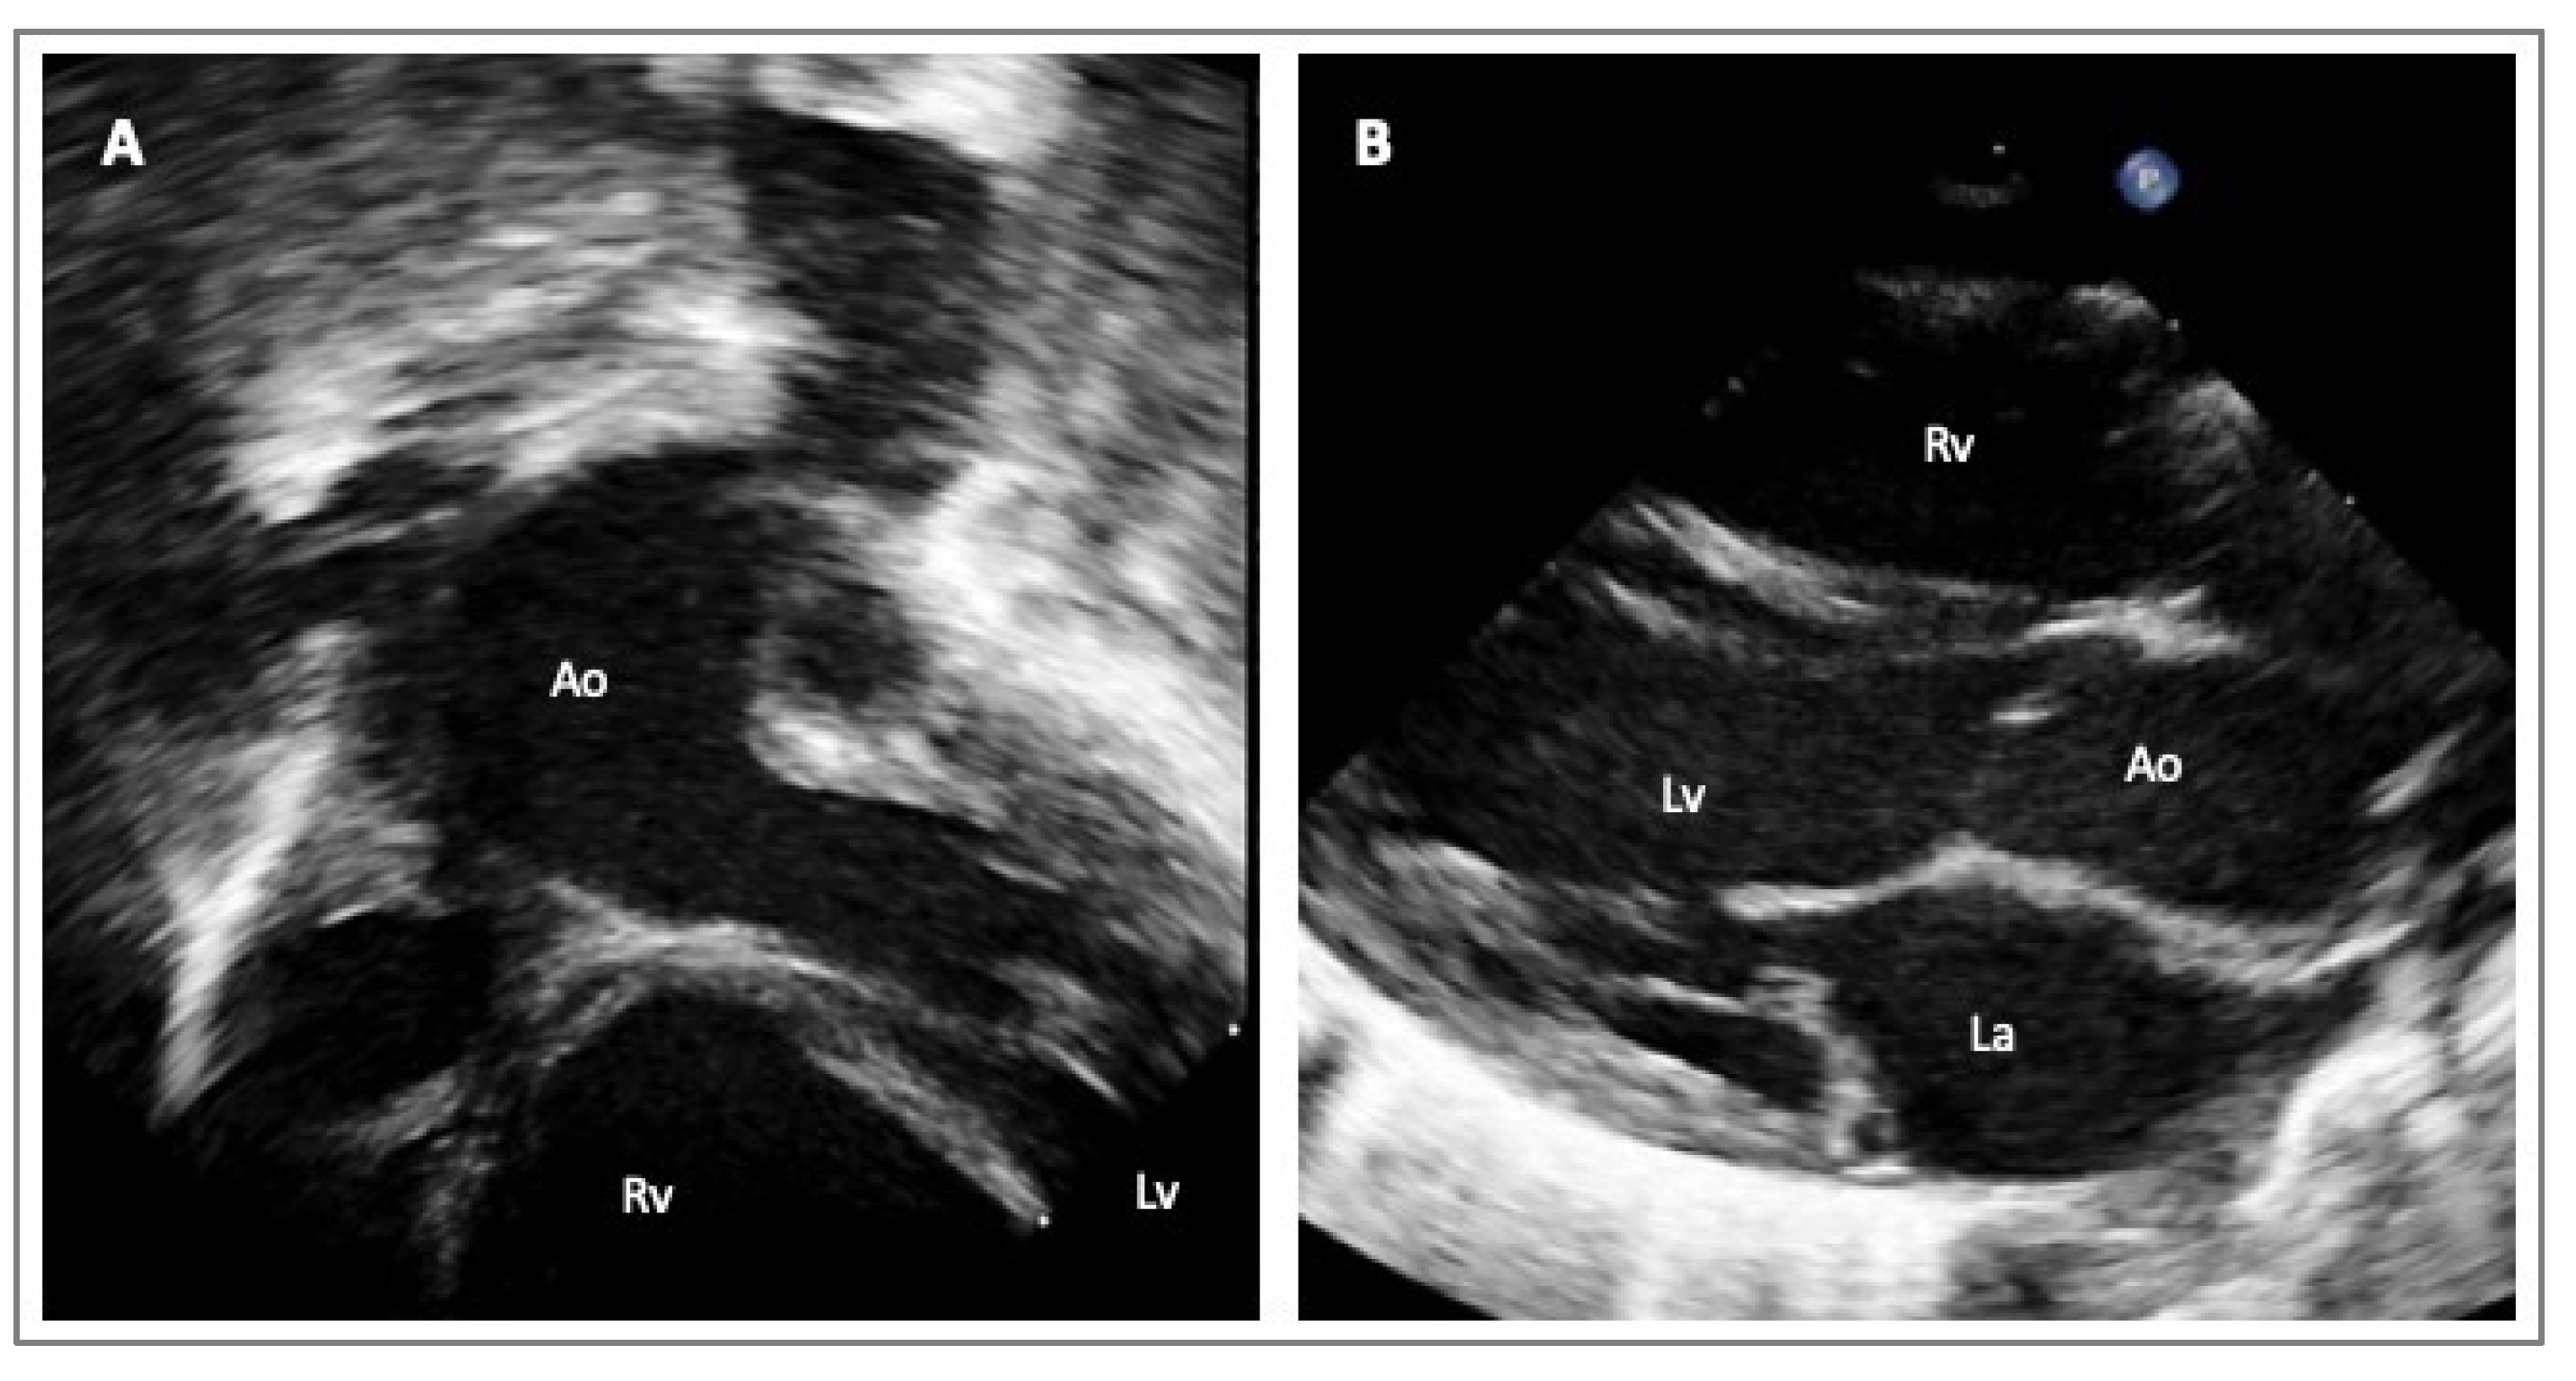

In everyday clinical practice, transthoracic echocardiography (TTE) is utilized to assess the proximal aortic dimensions via the TTE parasternal long axis view. In children, or when the acoustic windows are particularly suitable in adults, it is possible to visualize more aortic segments, i.e., the mid-distal ascending aorta, moving the transducer upper to the intercostal spaces, or in apical three-chambers and five-chambers views, and mainly in children, in the modified subcostal views. The aortic arch and the proximal descending aorta measurements can be achieved via the suprasternal window in adults and children (Figure 2) [32].

Figure 2.

Echocardiographic images of a one-year-old boy with suspected LDS/MS presenting with an isolated dilatation of the ascending aorta. Subcostal view of the aorta (Panel A); parasternal long axis view (Panel B). Legend: left ventricle (Lv); right ventricle (Rv); aorta (Ao); left atrium (La).